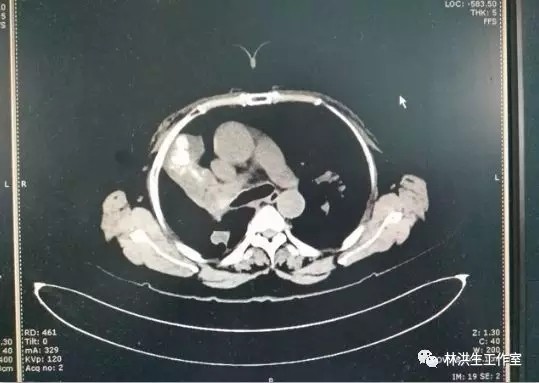

瘤体大小:中西医结合控制稳定

2016-2中药治疗后:右肺肿物4.0*3.5cm